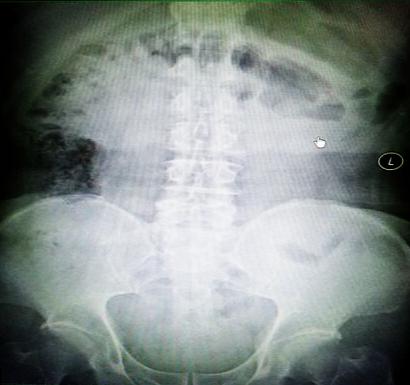

受試患者在結(jié)腸端端吻合術(shù)中,使用我司新研制產(chǎn)品達(dá)到了理想的預(yù)期效果。患者術(shù)后7天、14天X光片顯影,可降解腸道支架均能按研制設(shè)計的預(yù)期時間節(jié)點保持應(yīng)有強(qiáng)度,術(shù)后21天X光片顯示可降解腸道支架已完全破碎,并排出體外。在整個試驗過程中,病患無任何不良反映,耐受良好。